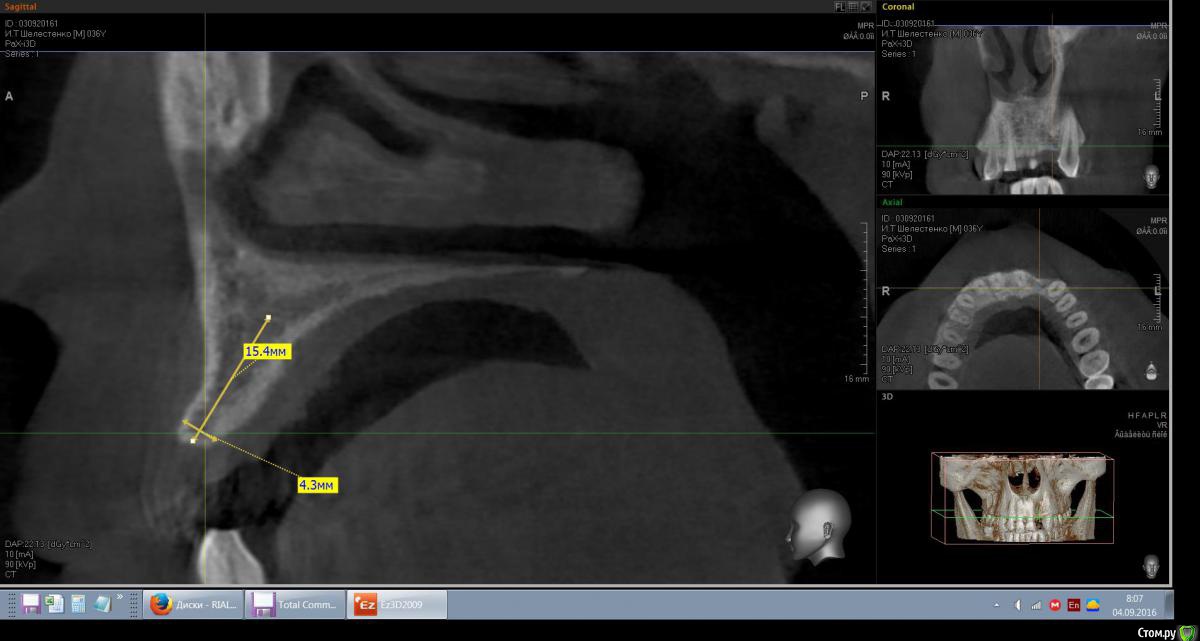

mann Опубликовано 4 сентября, 2016 Автор Поделиться Опубликовано 4 сентября, 2016 Доброе утро!Имеем такую ситуацию. Как лучше и правильно расположить имплант в данной ситуции? Ссылка на комментарий

red_butler Опубликовано 4 сентября, 2016 Поделиться Опубликовано 4 сентября, 2016 вот видите костное предложение на самом деле лучше. Только не нужно так небно ставить. Если сомневаетесь сделайте шаблон или пригласите на операцию ортопеда. И трансп добавьте. Ссылка на комментарий

red_butler Опубликовано 4 сентября, 2016 Поделиться Опубликовано 4 сентября, 2016 а что это? трансплантат.Мне больше нравится позиция на втором снимке, только вестибулярнее и не так глубоко, и я бы ложе готовил эспандерами или чуток расщепился бы Ссылка на комментарий

Эдгар Витальевич Опубликовано 22 октября, 2016 Поделиться Опубликовано 22 октября, 2016 Имплант 3.5мм не узковат будет? Такая же операция предстоит, ширина кости также 4.5 мм. Я планировал 4 мм ставить и костную пластику-титановую мембранку на имплант закрепить под фрмирователь. Ссылка на комментарий